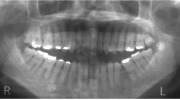

日本矯正歯科学会専門医課題症例(第7症例)

カテゴリー:開咬(overbiteがマイナスのもの)

出題の意味:開咬とは奥歯がしっかり咬んでも(完全に閉じても)、前歯が上下的に重ならないケースを言う。Overbiteがマイナスというのは全然重なっていないということを示しており、マイナス方向に数字が大きくなるほど症状はきつくなる。つまり完全に閉じているのに、前歯の隙間から舌が見えるような状態と言うこと。この症状は、舌や唇の筋力や動かし方に原因があるので、歯を矯正するだけではだめで、舌や唇の動かし方を正常にしないと後戻りを起こしやすい。専門医の試験では、治療後2年以上経過した資料を添付して、経過が良好であることを証明しないといけないので、後戻りしやすいこのケースは難易度が高いといえる。舌や唇の動かし方をトレーニングするのは、医院スタッフ(主に筋機能訓練療法を担当する歯科衛生士)であるので、医療機関の総合力が問われる項目である。

| 初診時